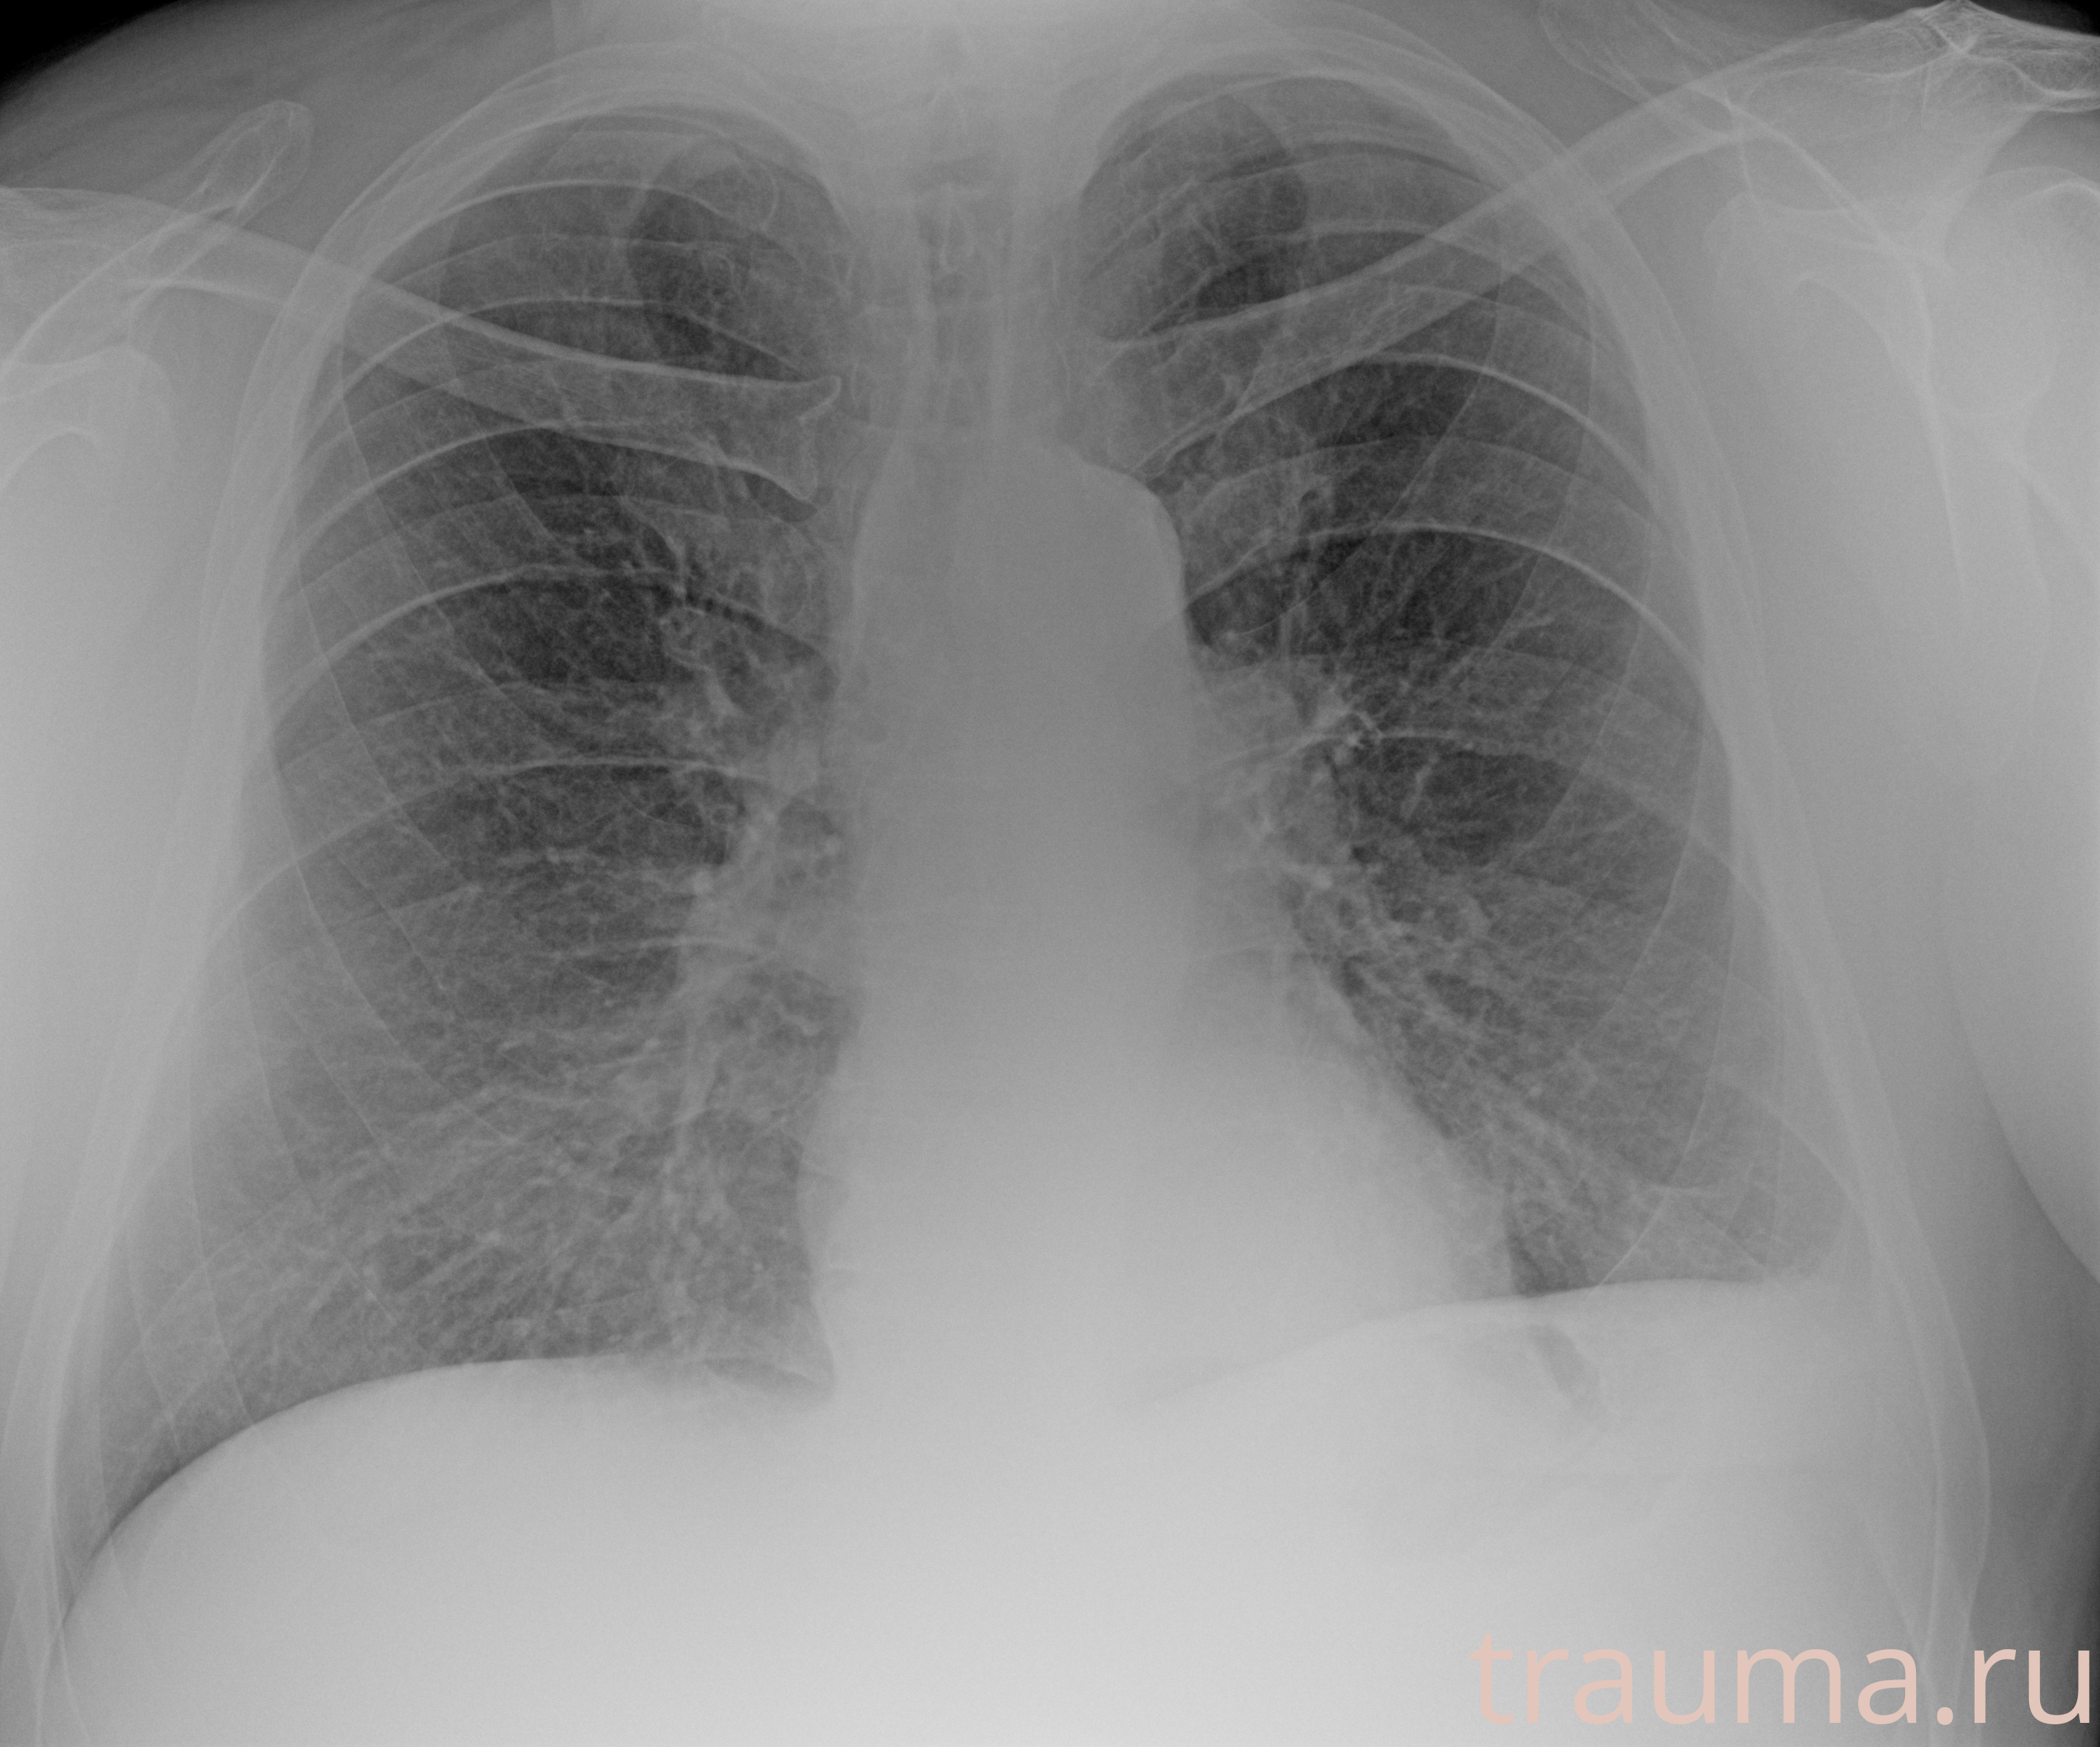

Рентгенограммы

Рентген на дому: по вашему адресу приезжает врач-рентгенолог, травматолог-ортопед с мобильным рентгеновским аппаратом, проводит диагностику травмы или заболевания, делает необходимые рентгенограммы, дает рекомендации по дальнейшему лечению. Получить качественные снимки в домашних условиях возможно благодаря уникальной методике, разработанной МосРентген Центром для института  Склифосовского

при переломе шейки бедра и пневмонии от компании МосРентген Центр - партнера Института имени Склифосовского